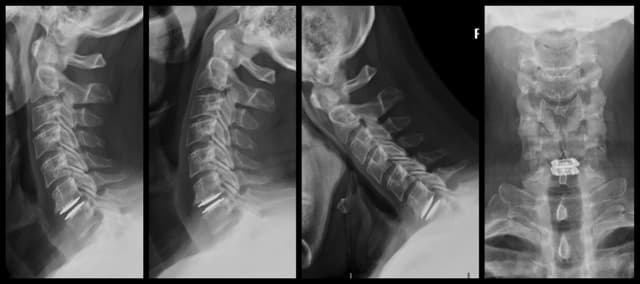

Imaging

Pre-op

Post-op